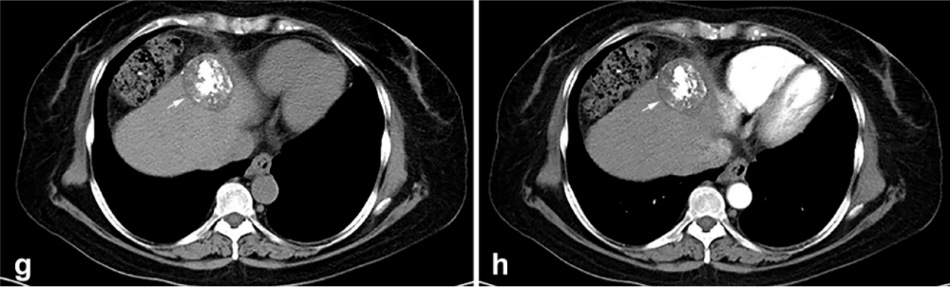

② 冷冻消融后 1 个月患者的增强 CT 显示HCC获得缓解。

③ 高危部位术中消融情况:冠状面CT图像经多平面重建冷冻消融时,肿瘤完全被冰球(箭头)覆盖。